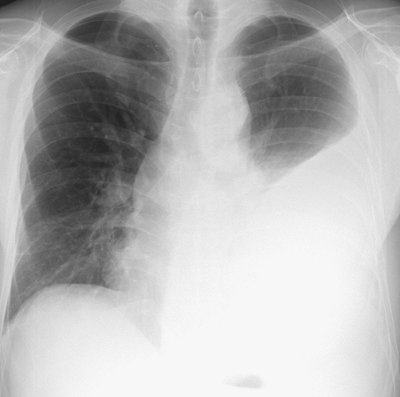

FIGURE 9-13. Tuberculous empyema. PA chest radiograph shows a large left pleural effusion. A large unilateral pleural effusion is worrisome for empyema, hemothorax, malignancy, or chylothorax.